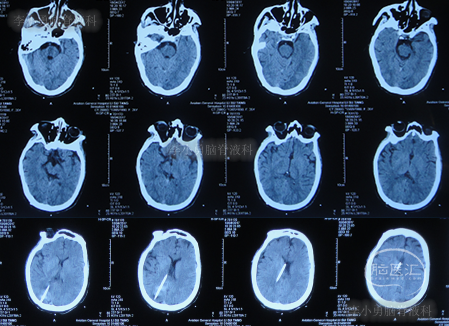

图-1:2016年3月18日头颅CT

第三家医院第2次建议回家观察1周后即2016年4月3日,症状仍未缓解反而越来越重,于是,就诊于第四家位于上海市徐汇区的某三甲医院,查头颅CT后(图-2)“认为无明显异常”,怀疑癫痫。